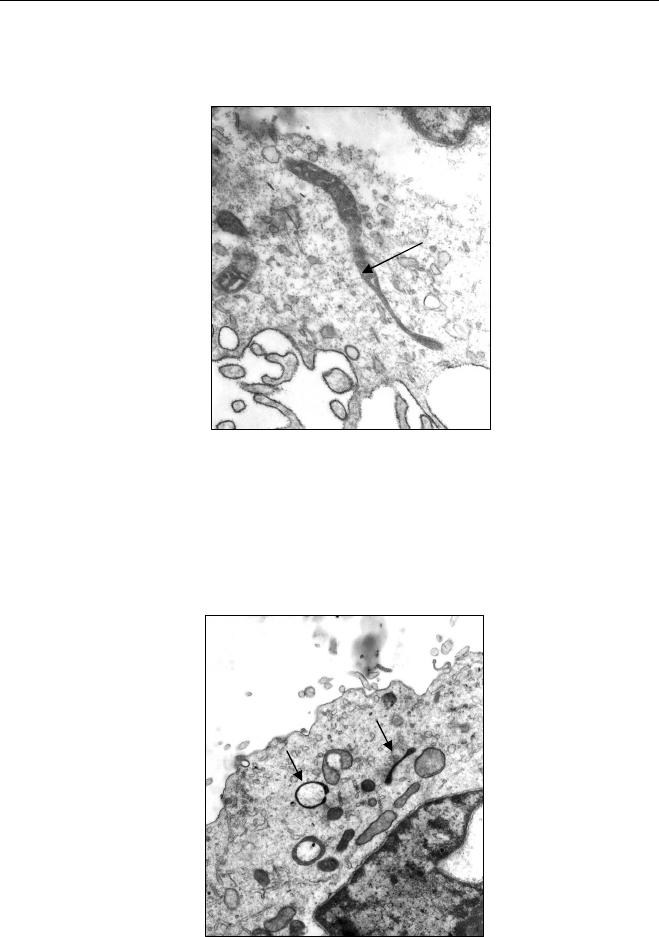

Para todas as reações, independente do primer, foi utilizado um

controle positivo (DNA do micro-organismo) e um controle negativo (mix). O

Materiais e Métodos

55

produto final das reações foi analisado em gel de agarose, corado por SYBr

Gold (Invitrogen) e visualizado à trans-iluminação pela ultravioleta.

4.13. Sequenciamento

As amostras que apresentaram positividade nas reações de PCR